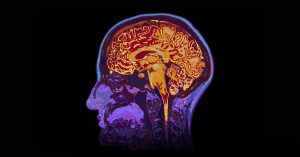

Intraoperative magnetic resonance imaging (iMRI) is one of the latest and cutting edge technology in neurosurgery. In this procedure, images of the brain are created during the surgery. Accurate pictures of the brain help the neurosurgeon in easy visualization during operations.